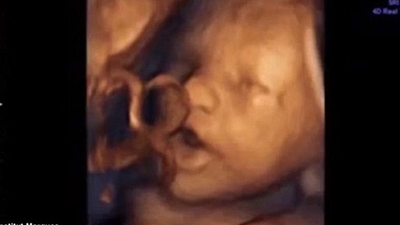

Bebekler annelerinin karnındayken tam 16 hafta sonra sesleri duyabiliyor. 14.39 haftalık hamileler üzerinde yapılan çalışmaya göre vajina içine yerleştirilen cihazla bebeklere müzik dinletildi.

Fetüslerden %87'sinin bu seslere tepki verdiği kaydedildi. Bebekleri verdiği tepkilerse videoyu izleyenleri gülümsetiyor.